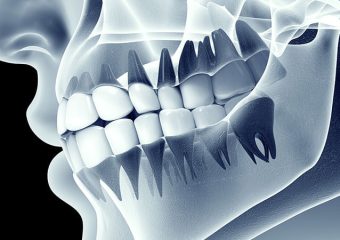

آشنایی با کاربرد دندان های انسان

بررسی کاربرد دندان های انسان

دندانها از مهمترین بخشهای بدن هر فرد هستند. انواع دندان ها علاوه بر نقش مهمی که در خوردن غذا دارند، در درست صحبت کردن به فرد کمک کرده و باعث زیبایی صورت نیز میشوند. تقریبا تمام مهرهداران دارای دندانهایی با ساختار سفید رنگ هستند که هنگام باز شدن دهان قابل رویت هستند. در این نوشته از سایت دکتر ندا مکانیک بهترین دندانپزشک اصفهان کاربرد دندان های انسان را مورد بررسی قرار می دهیم. انسان تنوع بی نظیری از دندانها را دارد که با رشد دندانهای شیری آغاز و به مرور زمان با دندانهای اصلی جایگزین میشوند.

ساختمان انواع دندان

تمام دندانهای موجود در فک افراد از نظر ساختمان دارای دو بخش متفاوت هستند. این دو شامل بخش بیرونی که در ظاهر نیز مشخص است و بخش داخلی که درون لثه قرار میگیرد. ترکیب این دو در کنار یکدیگر دندان را تشکیل داده که به جوییدن غذا کمک میکند.

- قسمت بیرونی دندان را تاج میگویند که شامل مینا، عاج و مغز دندان است.

- قسمت داخلی دندان شامل بخشهای مختلفی مانند سمان، پالپ و همچنین لیگامنهای دور دندان است.

معرفی انواع دندانها

دندانها به دستههای مختلفی تقسیم میشوند که در ادامه ذکر شده است.

دندانهای پیشین

به دندانهایی تیزی که در جلوی دهان قرار گرفتهاند، دندانهای پیشین گفته میشود. از این دندانها برای گاز زدن غذا و خوراکیها استفاده میشود. این دندانها که به آنها دندان قدامی نیز گفته میشود، کاملا صاف با لبهای تیز هستند. تمام افراد دارای 8 دندان پیشین هستند. چهار دندان به صورت دوتایی در فک بالا و پایین قرار گرفته و در کنار آنها یک دندان دیگر وجود دارد.

دندانهای نیش

این دندانها، دندانهای تیز و نوک داری هستند که در کنار دندانهای پیشین قرار میگیرند. ظاهر این دندانها شبیه به نیش است که آنها را دندان انیاب یا دندان ناب نیز مینامند. دندانهای نیش از سایر دندانها بلندتر هستند که برای پاره کردن خوراکیها مورد استفاده قرار میگیرند. هر فرد 4 دندان نیش دارد که دندانهای نیش دائمی در سن 9 تا 12 سال رشد میکنند. دنداهای نیش تحتانی از دندانهای نیش فوقانی زودتر رشد میکنند.

دندانهای آسیا

بزرگترین دندانها در تمام افراد، دندانهای آسیا هستند. دندانهایی با سطح بزرگ و تخت که دارای برآمدگیهایی برای خرد کردن و جویدن غذا هستند. هر فرد بزرگسال 12 دندان آسیا و کودکان نیز هشت دندان آسیا دارند که بین فک بالا و پایین تقسیم میشوند. دندانهای عقل، آخرین دندانهای آسیا هر فرد هستند که تقریبا بین سن 17 تا 21 سالگی رشد میکنند.

دندانهای آسیا کوچک

دندانهای آسیا کوچک که به آنها دندانهای دو پایه گفته میشود، دندانهایی بزرگتر از دندانهای نیش و پیشین هستند. این دندانها نیز با داشتن برآمدگیهایی که جویدن غذا کمک میکنند. هر فرد بزرگسال 8 دندان آسیا کوچک دارد. آسیا های کوچک اول و دوم در کنار دندانهای نیش قرار گرفتهاند. این دندانها به صورت دائمی هستند و کودکان دندان آسیا کوچک شیری ندارند.

دندان عقل

دندانهای عقل آخرین دندانهایی هستند که در فک افراد بزرگسال رشد میکنند. برخی از افراد چهار دندان عقل دارند، برخی تعداد کمتری و در برخی از افراد این دندانها در استخوان فک باقی مانده و هرگز رشد نمیکنند. اگر دندان عقل به خوبی رشد نکند یا نصف آن در لثه باقی بماند، مشکلاتی برای فرد ایجاد کرده و باعث عفونتهای لثهای میشود.

همچنین اگر فک جای کافی برای رشد دندان عقل نداشته باشد، رشد این دندانها به دندانهای دیگر آسیب رسانده و باعث ایجاد درد و تورم میشود. در صورت بروز این مشکلات و درد و یا عفونت در آنها حتما به دندانپزشک مراجعه کنید. به دندان عقل مولر سوم نیز گفته میشود که معمولا دارای سه یا چهار کانال هستند.

دندانها از مهمترین و کاربردیترین عضوهای بدن هستند که برای جویدن غذا مورد استفاده قرار میگیرند. علاوه بر آن قرارگیری آنها باعث ایجاد ظاهر زیبا در فک و صورت میشود. دندانها انواع مختلفی دارند که هر کدام در سنین مختلف رشد کرده و کاربرد خاص خود را دارند.